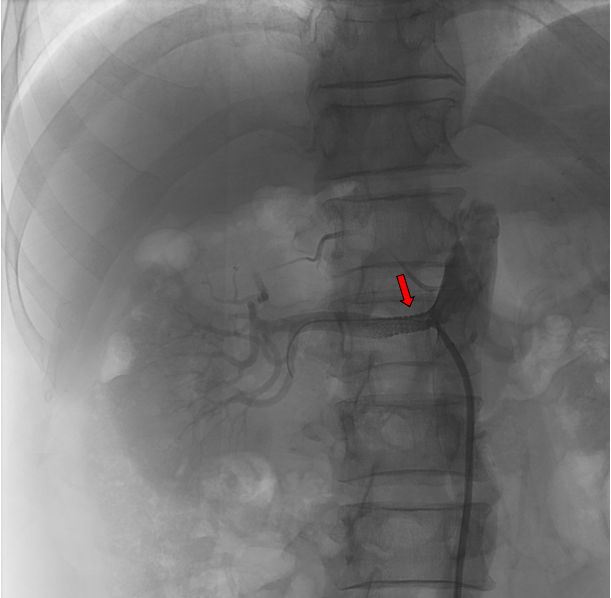

患者于4月9日上午送介入手术室行右肾动脉支架置入术。术中造影显示右肾动脉起始段明显狭窄,狭窄约90%,予置入肾动脉裸支架(7*19mm)后,造影显示右肾动脉狭窄解除,支架扩张良好,右肾灌注恢复。

红色标记为支架置入前,右肾动脉明显狭窄